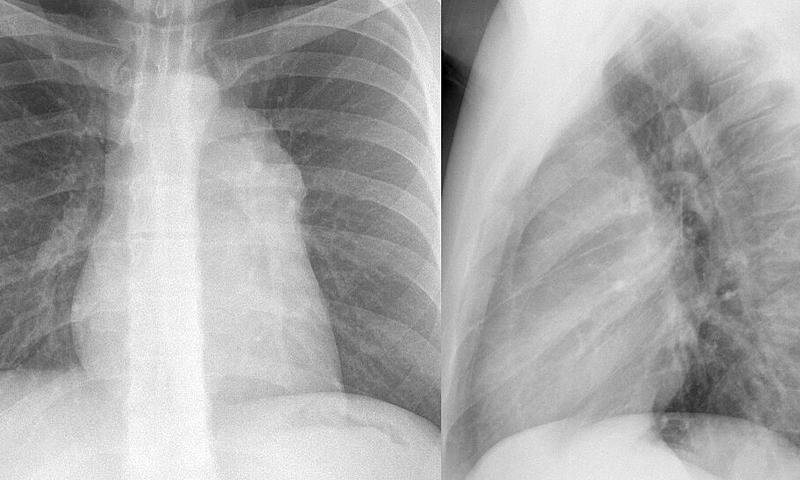

Case 1c Thymoma

Case 1c

Thymoma